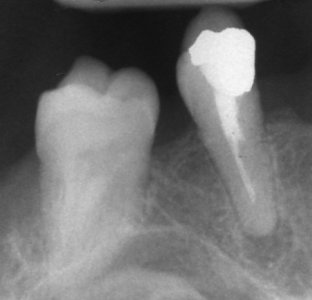

Запълване с препресване

Ендодонтия